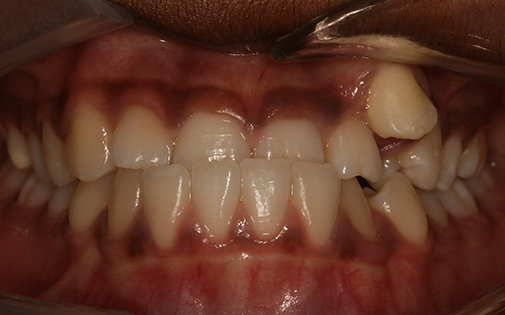

This teenage patient had a very crowded top left canine tooth as well as an underbite. He was successfully treated with Invisalign clear aligners in 22 months.